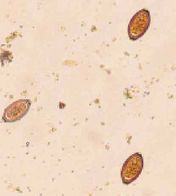

吸虫類